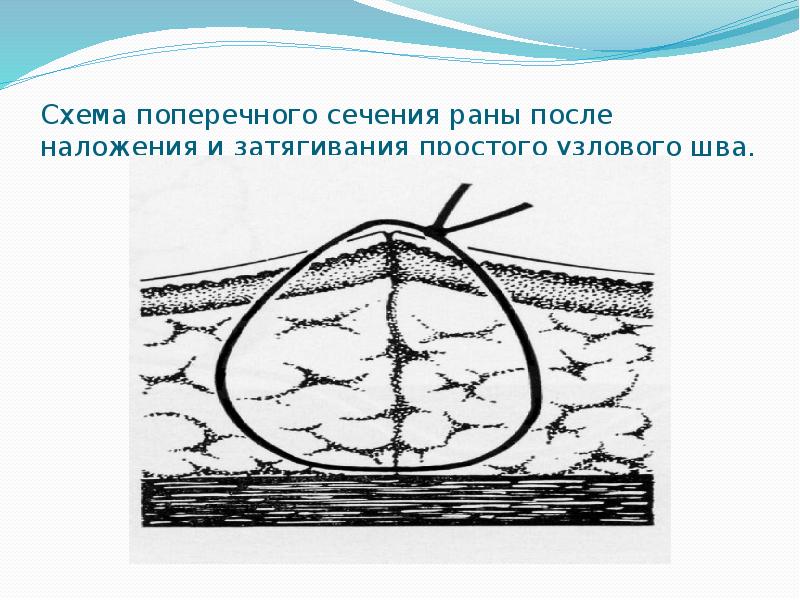

- 22. Схема поперечного сечения раны после наложения и затягивания простого узлового шва.